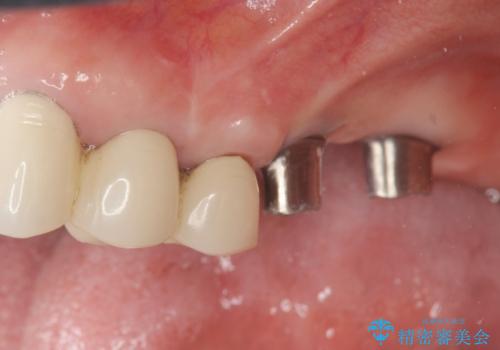

遊離端ブリッジ インプラント補綴への設計変更

- 他院で治療した左上のセラミック部位の痛みを訴えて来院されました。

支台となる小臼歯に過大な負担のかかる遊離端ブリッジが装着されていたため、義歯かインプラントを用いた再補綴計画を提案しよりしっかりと噛めるインプラント治療をご希望されました。

力学的に無理のある遊離端ブリッジをインプラントを用いて長期的な予後を見込める補綴状態へと改善しました。